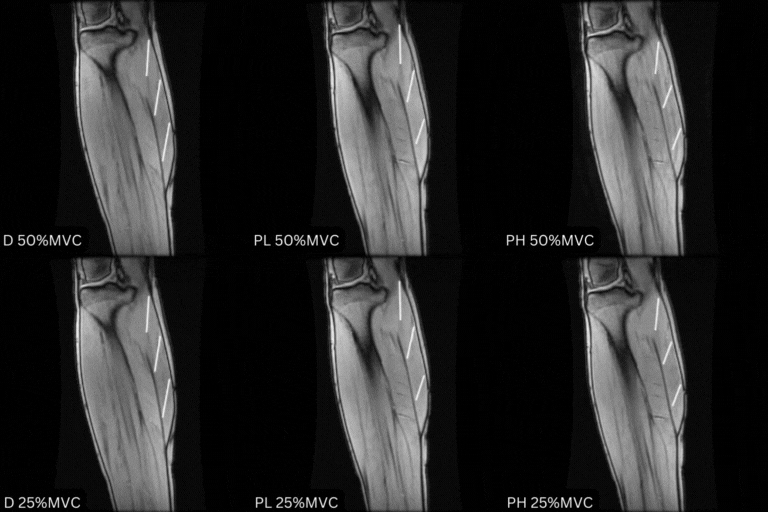

Quantitative analysis of muscle strain via MRI image processing

Developed Python MRI image processing methods to study muscle strain. Examined the effects of different ankle angles and exertion levels on strain.

Muscle strain aligned in the direction of muscle fibers

Projected strain for each voxel in MRI images in the direction of muscle fibers. Compared results for young and old subjects.

Designed Python NumPy scripts for processing and integrating MRI datasets (DICOM, CSV). Developed Python NumPy pipelines to analyze processed MRI data to compute muscle strain. Executed Python pandas statistical analysis of fiber strain across patients and foot angles